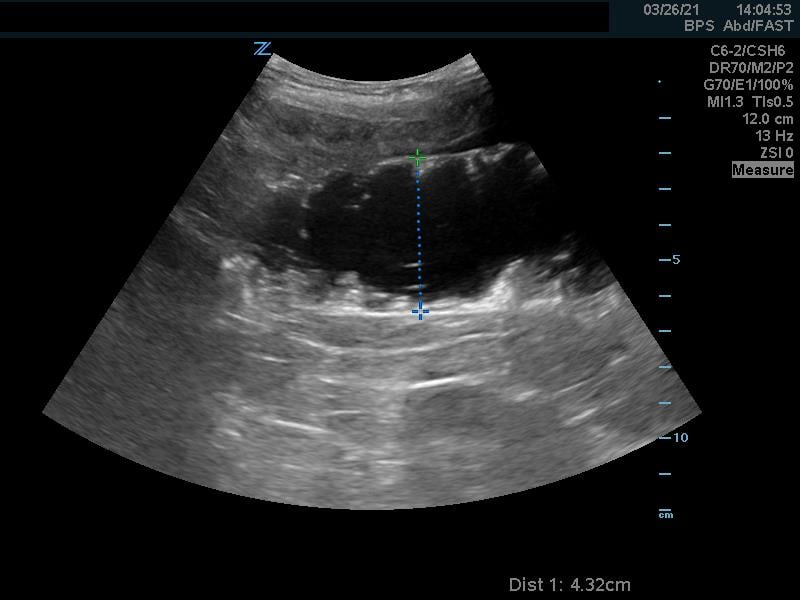

- When the intussusception is seen it should be imaged in both long (Fig. 6a, Video 3) and short (Fig. 6b, Video 3) axis.

- In the long axis, a kidney-shaped mass, which is often called the pseudokidney sign, is seen. This is an oblique view of the invaginated bowel. (Fig. 6a)

- Figure 6a. Image in long axis of ileocolic intussusception